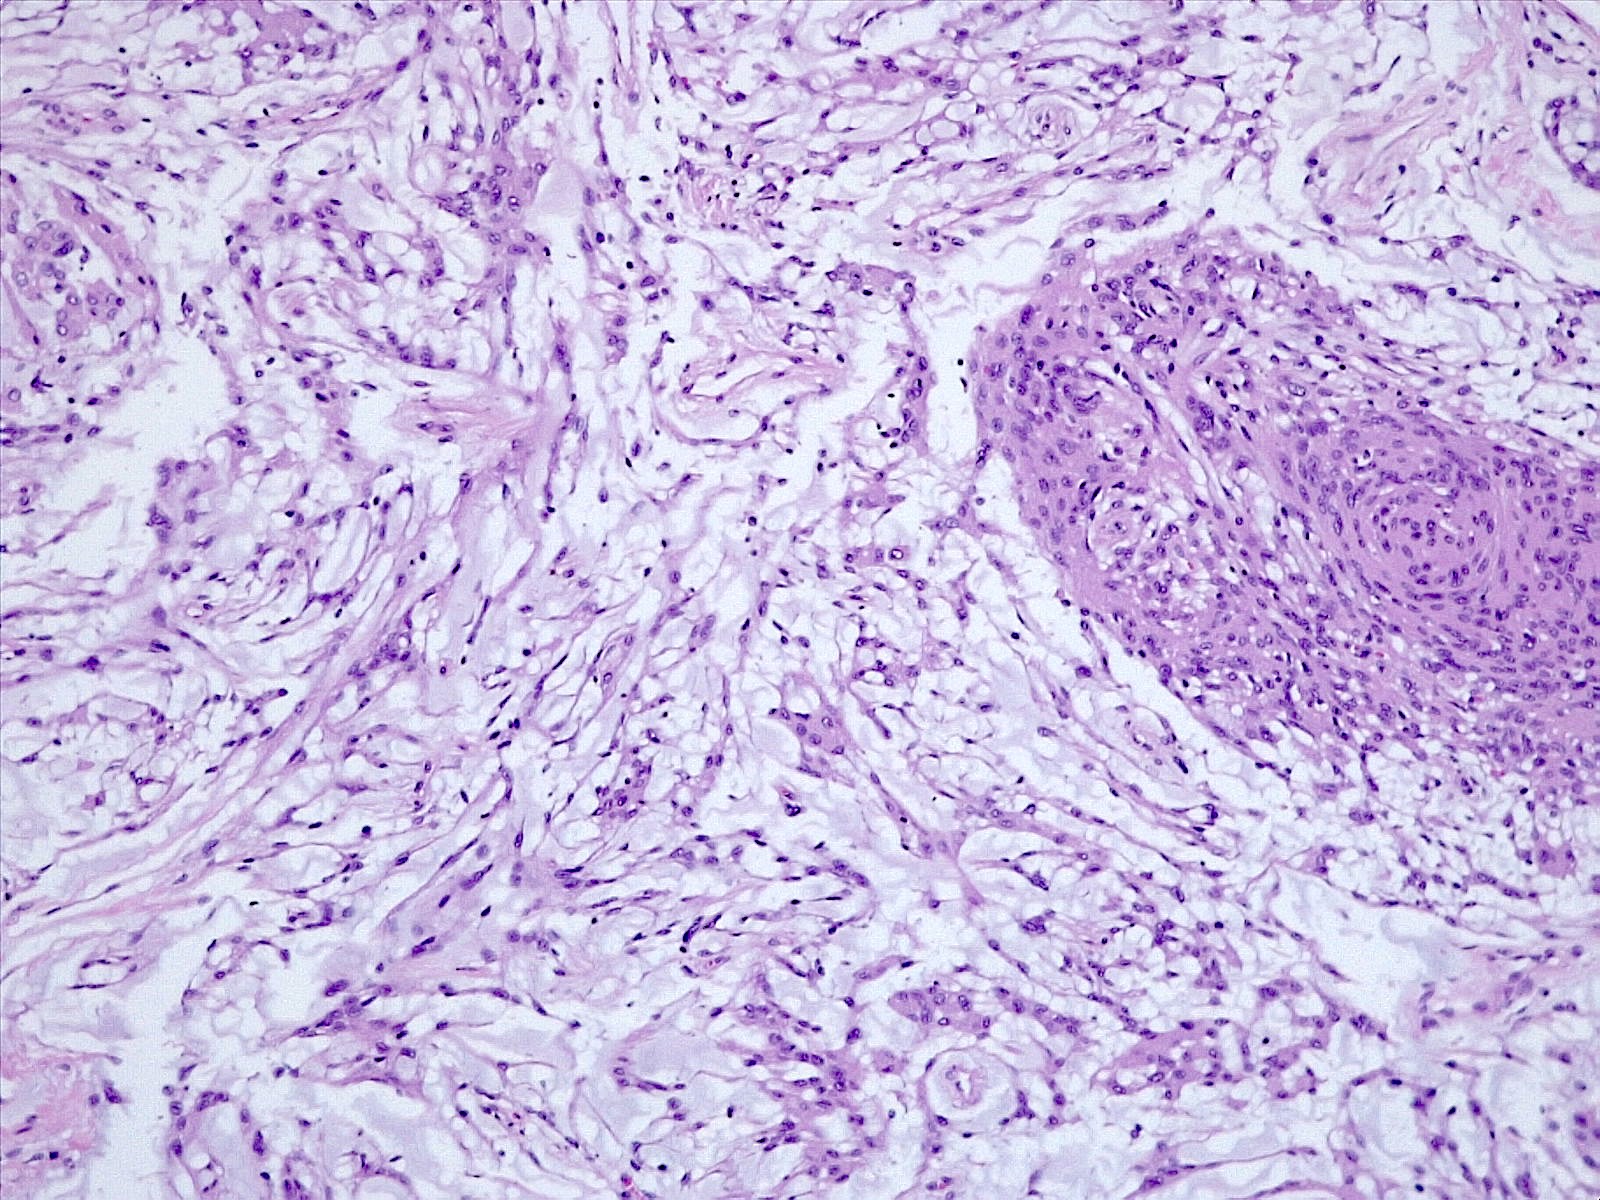

Microscopic (histologic) description

- Histologically reminiscent of chordoma, consisting of epithelioid cells or spindle cells (often partly vacuolated) that are arranged in cords within a pale basophilic myxoid matrix (Am J Surg Pathol 2000;24:899, J Neurooncol 2010;100:465, Histopathology 2013;62:1002)

- Interspersed areas of more typical meningioma are frequent but pure chordoid cases may be seen (Am J Surg Pathol 2000;24:899, J Neurooncol 2010;100:465, Histopathology 2013;62:1002)

- Atypical features may be seen, including mitoses, brain invasion, spontaneous necrosis, macronucleoli, increased cellularity, sheeting or small cells with a high N:C ratio (Am J Surg Pathol 2000;24:899, Acta Neuropathol Commun 2022;10:56, Histopathology 2013;62:1002)

Microscopic (histologic) images